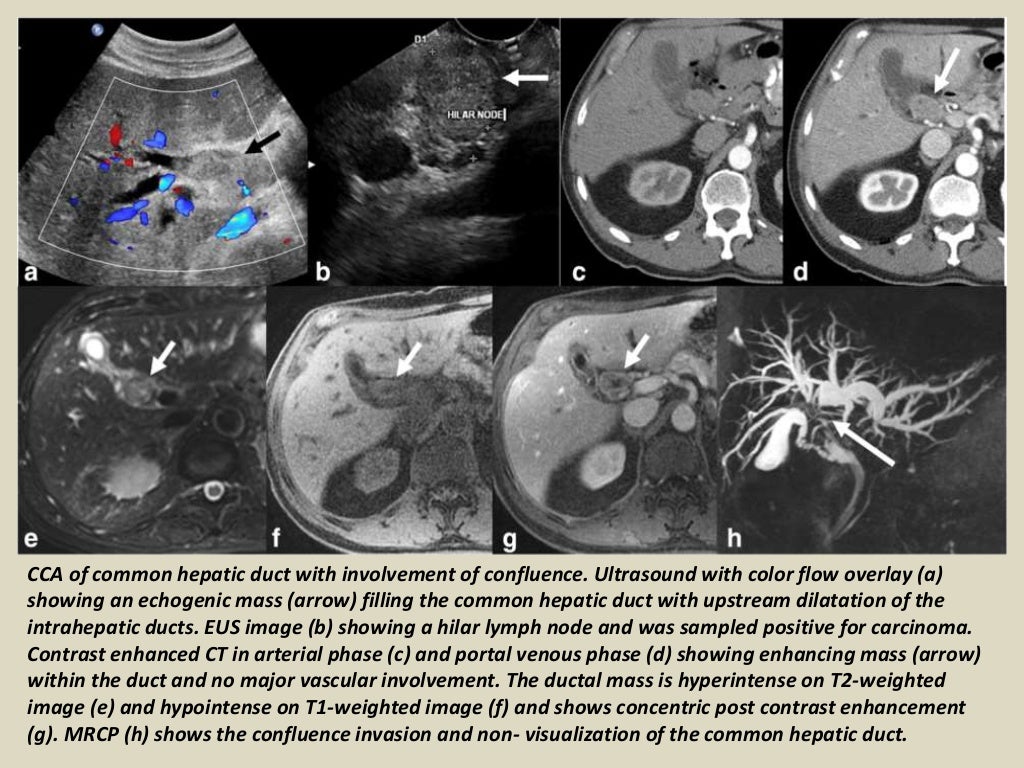

Presentation1.pptx, radiological imaging of cholangiocarcinoma. Cholangiocarcinoma Eovist Radiology — gadoxetate disodium (also known by the tradenames primovist in europe and australia/new zealand and eovist in the united states) is a. Cholangiocarcinoma Eovist Radiology.